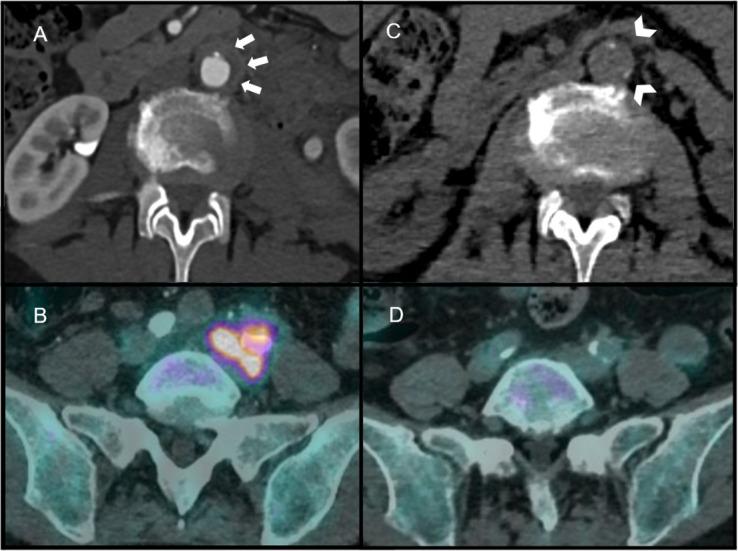

Eosinophilic granulomatosis with polyangiitis (EGPA) is an ANCA-associated vasculitis that affects small size vessels. Only four cases of periaortitis associated with EGPA have been reported in the literature. We report the case of a 67-year-old woman with EGPA who developed periaortitis 11 months after the initiation of dupilumab for uncontrolled asthma with hypereosinophilia. Complete remission of the periaortitis, and of EGPA, was obtained after switching from dupilumab to mepolizumab combined with oral prednisone therapy. Dupilumab has been associated with hypereosinophilia, that is usually asymptomatic and transitory, but symptomatic cases including EGPA were exceptionally reported. Although causality has not yet been established, caution is advisable when prescribing dupilumab for uncontrolled asthma with features that might suggest EGPA.

嗜酸性肉芽肿伴多血管炎(EGPA)是一种与抗中性粒细胞胞浆抗体(ANCA)相关的小血管血管炎。文献中仅报道了 4 例与 EGPA 相关的主动脉旁炎病例。我们报告了一例 67 岁女性的病例,该患者因未控制的哮喘伴嗜酸性粒细胞增多,在接受度普利尤单抗治疗 11 个月后出现主动脉旁炎。在将度普利尤单抗转换为美泊利珠单抗联合口服泼尼松治疗后,主动脉旁炎和 EGPA 完全缓解。度普利尤单抗与嗜酸性粒细胞增多有关,通常无症状且短暂,但也有例外报告出现包括 EGPA 在内的有症状病例。尽管尚未确定因果关系,但在为可能提示 EGPA 的特征性未控制哮喘开具度普利尤单抗处方时应谨慎。